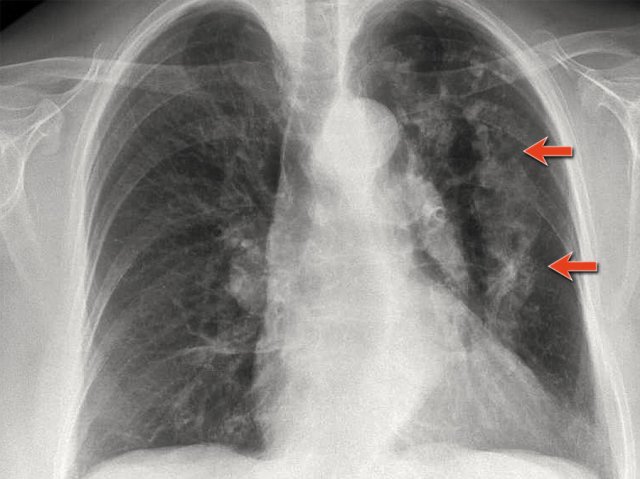

First study the CXRs.

There is a subtle consolidation in the left lower lobe in the hidden area behind the heart.

Again there is increased density over the lower vertrebral region.